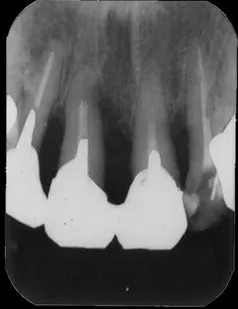

[症例2](エムドゲインを用いた治療例)

歯周病が進行して歯の周囲の骨が溶けてなくなっています。

全体の炎症を抑え、エムドゲインを用いて歯周外科処置を行い、歯茎が健康を取り戻した後に機能的なセラミックの冠を入れて治療しました。

レントゲン写真では治療前よりかなり骨が増えているのがわかります。

• 治療期間:約1.5年

• 治療費:60万円

• 治療回数:20回